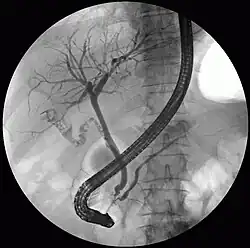

Colangiopancreatografía retrógrada endoscópica

El estudio diagnóstico y terapéutico del páncreas y la vía biliar (colangiopancreatografía retrógrada endoscópica), combina la endoscopia con los Rayos X para su realización; el gastroenterólogo es el especialista que suele practicarlo. Se suele abreviar CPRE o ERCP (del inglés Endoscopic Retrograde Cholangiopancreatography).

Al canular el ámpula de Vater se puede inyectar medio de contraste y es allí cuando entran a funcionar los Rayos X, por medio de fluoroscopía que es un estudio dinámico. Se observa como en una película cómo avanza el medio de contraste y dibuja la vía biliar o pancreática. Permite determinar su anatomía y detectar deformidades, presencia de cálculos, de tumores o de estrecheces. Si se detecta alguna anormalidad, con frecuencia se pasa a la fase terapéutica.